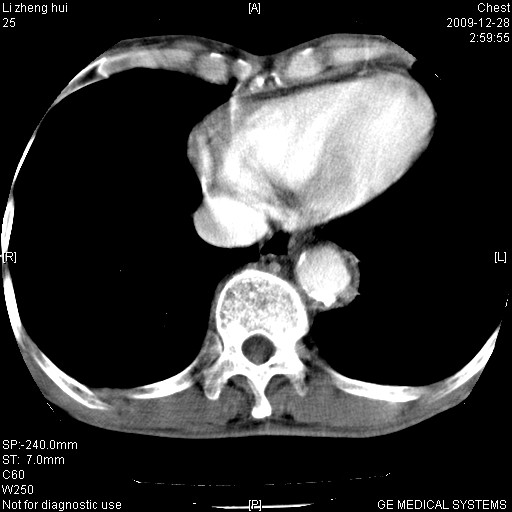

标题: CT23859:胸主动脉瘤

男  79岁 胸部痛急诊入院,晚上做的增强

考虑主动脉瘤?(增粗、钙化、壁血栓?)

支持,另有肝囊肿。

动脉瘤伴附壁血栓

1)考虑胸主动脉壁间血肿或夹层动脉瘤。2)多发性肝囊肿。

1)考虑胸主动脉附壁血栓或夹层动脉瘤。2)多发性肝囊肿。